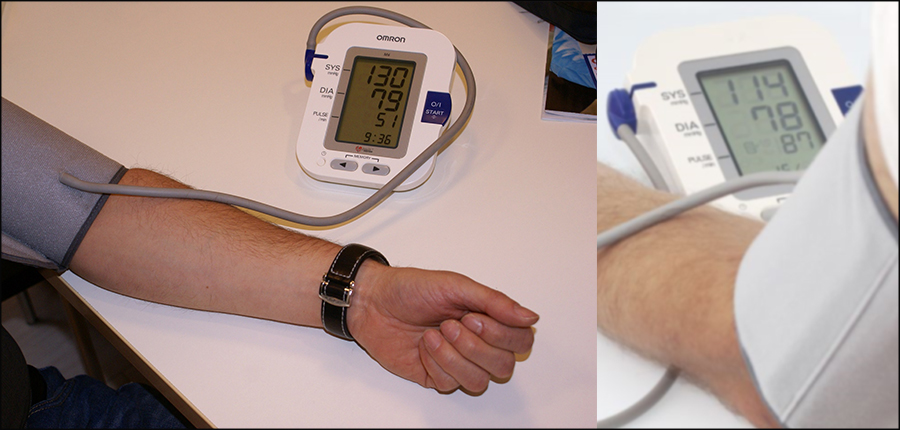

L’Hypertension artérielle (HTA) : Comment reconnaitre cette maladie silencieuse ?

Aujourd’hui, de plus en plus de personnes sont atteintes d’hypertension artérielle, mais s’ignorent. Des centaines voire des milliers de personnes développent des complications, du fait d’une hypertension artérielle non diagnostiquée ou mal prise en charge. Dans une série d’articles, le site de la médecine du 21ème siècle, www.sante21.ma, essayera de répondre à des questions essentielles sur cette maladie silencieuse, avec une spécialiste, Dr Nadia SRAIRI. Elle est spécialiste des maladies cardio-vasculaires et diplômée dans l’échographie et la réadaptation cardiaque de la Faculté de Médecine de l’Université Victor Segalen de Bordeaux. Dans ce premier entretien, Dr Nadia SRAIRI, attire sur le fait que, les maux de tête matinaux, les vertiges, les saignements de nez, une impression de voir des mouches voler devant ses yeux, les bourdonnements dans les oreilles, les rougeurs au visage, un essoufflement anormal ou un besoin fréquent d'uriner la nuit, sont autant de signes d’alerte, qu’une personne, femme ou homme, développe sournoisement une hypertension artérielle.